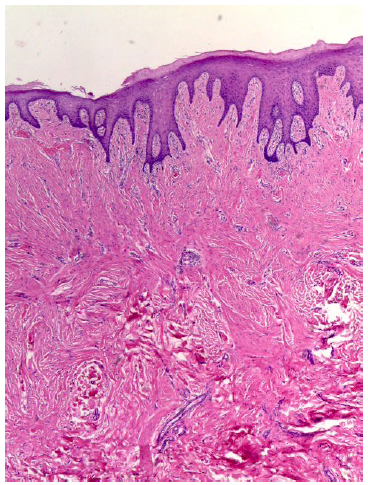

Histológicamente se caracteriza por ser una lesión de tejido conectivo denso, no encapsulada, formado por fibras colágenas (3,5,10,11,12,13,14,15), y algunas veces hialinizado. (11) La superficie epitelial es usualmente atrófica (11,12), cubierta por un epitelio hiperqueratósico (5,11,14,15), la cual puede estar también ulcerada debido al trauma constante (3,5,11,14,15), provocando un exceso de queratina y edema intracelular de las capas superficiales (11), como se observa en la figura 2.

Al Dr. Diego Guillén Colombari por su colaboración con el estudio histopatológico y la respectiva imagen.